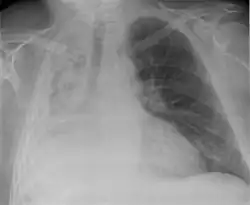

| Atelectasis of a person's right lung | |

Clinically significant atelectasis is generally visible on chest X-ray; findings can include lung opacification and/or loss of lung volume. Post-surgical atelectasis will be bibasal in pattern. Chest CT or bronchoscopy may be necessary if the cause of atelectasis is not clinically apparent. Direct signs of atelectasis include displacement of interlobar fissures and mobile structures within the thorax, overinflation of the unaffected ipsilateral lobe or contralateral lung, and opacification of the collapsed lobe. In addition to clinically significant findings on chest X-rays, patients may present with indirect signs and symptoms such as elevation of the diaphragm, shifting of the trachea, heart and mediastinum; displacement of the hilus and shifting granulomas.[13]